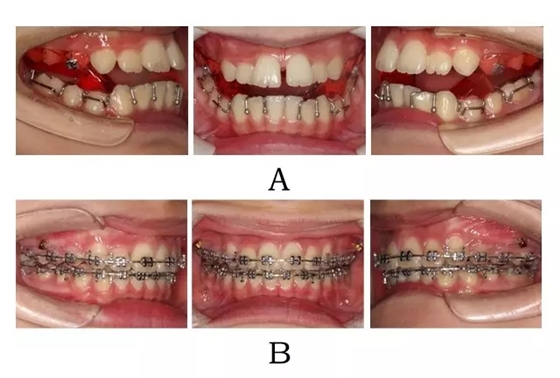

生長(zhǎng)發(fā)育高峰期青少年,最佳方案是應(yīng)用 SGTB 矯形技術(shù),在抑制上頜的同時(shí),釋放后退的下頜向前,并引發(fā) TMJ 局部改建,鞏固由于頜位重建而取得的前牙覆合覆蓋的糾正及后牙在中性關(guān)系下的尖窩對(duì)接[9](圖3-2;3-3)。

圖3-2:頜位性突面畸形SGTB矯形及后期常規(guī)固定矯治。

(A)SGTB矯形 (B)后期固定矯治

Figure 3-2. SGTB therapy for mandibular positional prognathism. (A) SGTB orthopedics at early stage. (B) Fixed orthodontics at late stage.